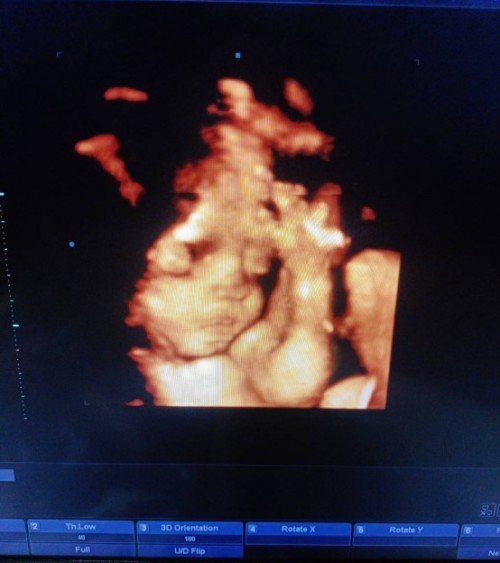

ซาวตอน30w